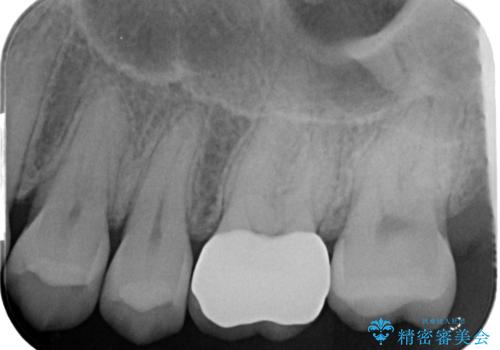

- 金の詰め物の中が黒く透けていて虫歯があるので拡大鏡下で外し、虫歯がない事を確認した後、被せ物で治療しました。

- ジルコニアクラウンスタンダード・仮歯 12.1万円 e-maxインレー 7.7万円費用は治療当時の料金となります

適合の良いクラウン、詰め物が入りました。

適合が良いことで虫歯の再発のリスクが低くなります。